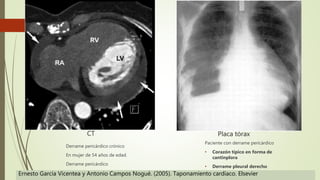

Placa tórax

Paciente con derrame pericárdico

• Corazón típico en forma de

cantinplora

• Derrame pleural derecho

CT

Derrame pericárdico crónico

En mujer de 54 años de edad.

Derrame pericárdico

Ernesto García Vicentea y Antonio Campos Nogué. (2005). Taponamiento cardíaco. Elsevier

Placa tórax Paciente conderrame pericárdico • Corazón típico en forma de cantinplora • Derrame pleural derecho CT Derrame pericárdico crónico En mujer de 54 años de edad. Derrame pericárdico Ernesto García Vicentea y Antonio Campos Nogué. (2005). Taponamiento cardíaco. Elsevier